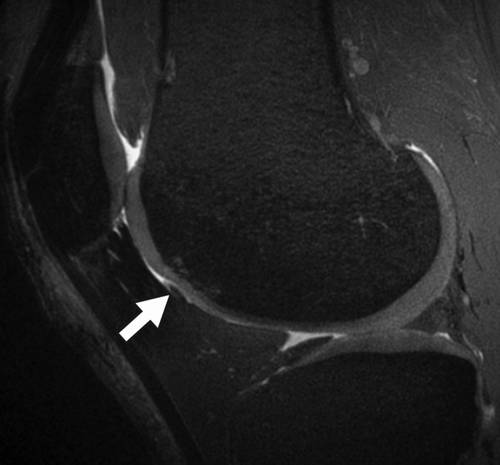

図12 Kellgren Lawrence による膝OA 重症度分類4 MRI を用いた臨床診断もさまざまな定量的な評価方法が報告されている813.先行研究 においては,関節軟骨変性の検出についての報告が多いが半月板を扱っているものもいく12骨挫傷および半月板損傷 膝痛の原因は様々ですが、膝関節内の半月板・軟骨・靱帯などの状態を調べるのに、MRI検査は非常に役立ちます。 この症例では脛骨の骨挫傷(→)と内側半月板後角損傷(*→)を認めます。 MRIトップ | 1乳腺疾患 | 2脳2 膝の固定方法 膝関節mriで最も重要な関節内構成要素のひとつに前十字靱帯(acl)がある。 mri機器に付属する膝用コイルのほとんどは円筒形であるが(図1),通常,円筒 形コイルに膝をセットし固定すると,膝は伸展位になる傾向がある。この場合,

膝关节骨挫伤的mri征象研究及临床意义